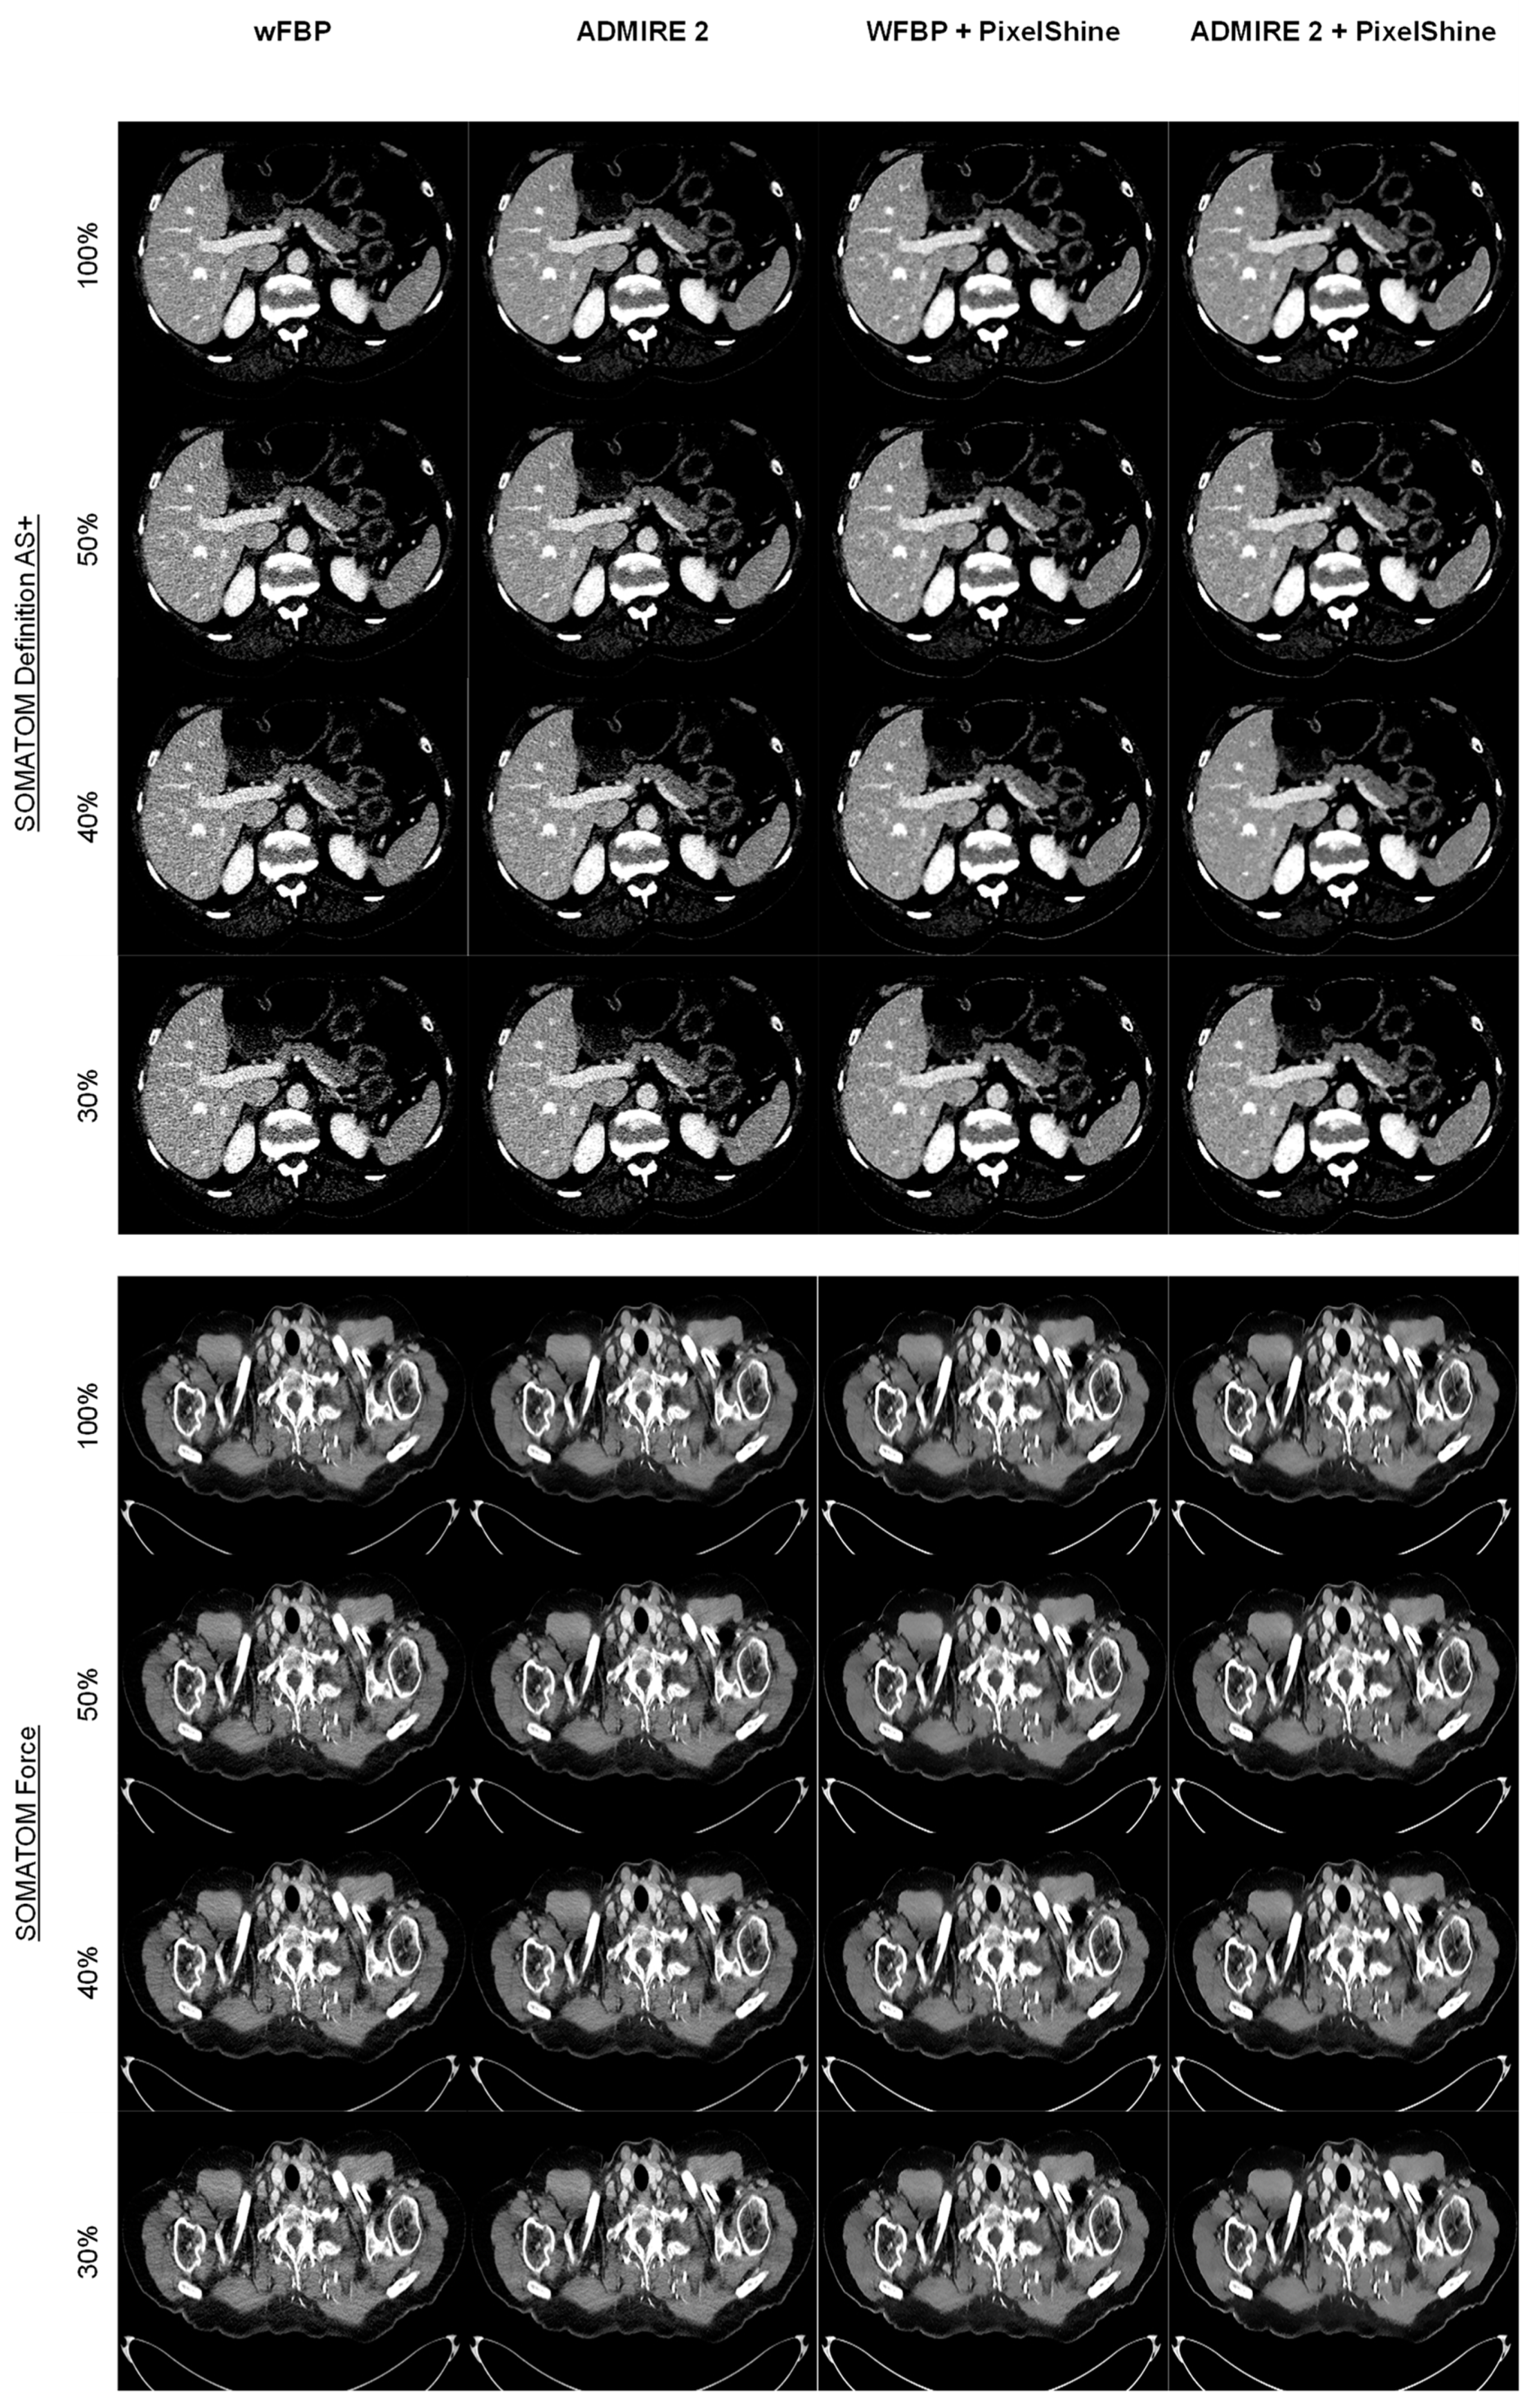

3.2.1. Subjective Image Quality

3.2.2. Objective Image Quality